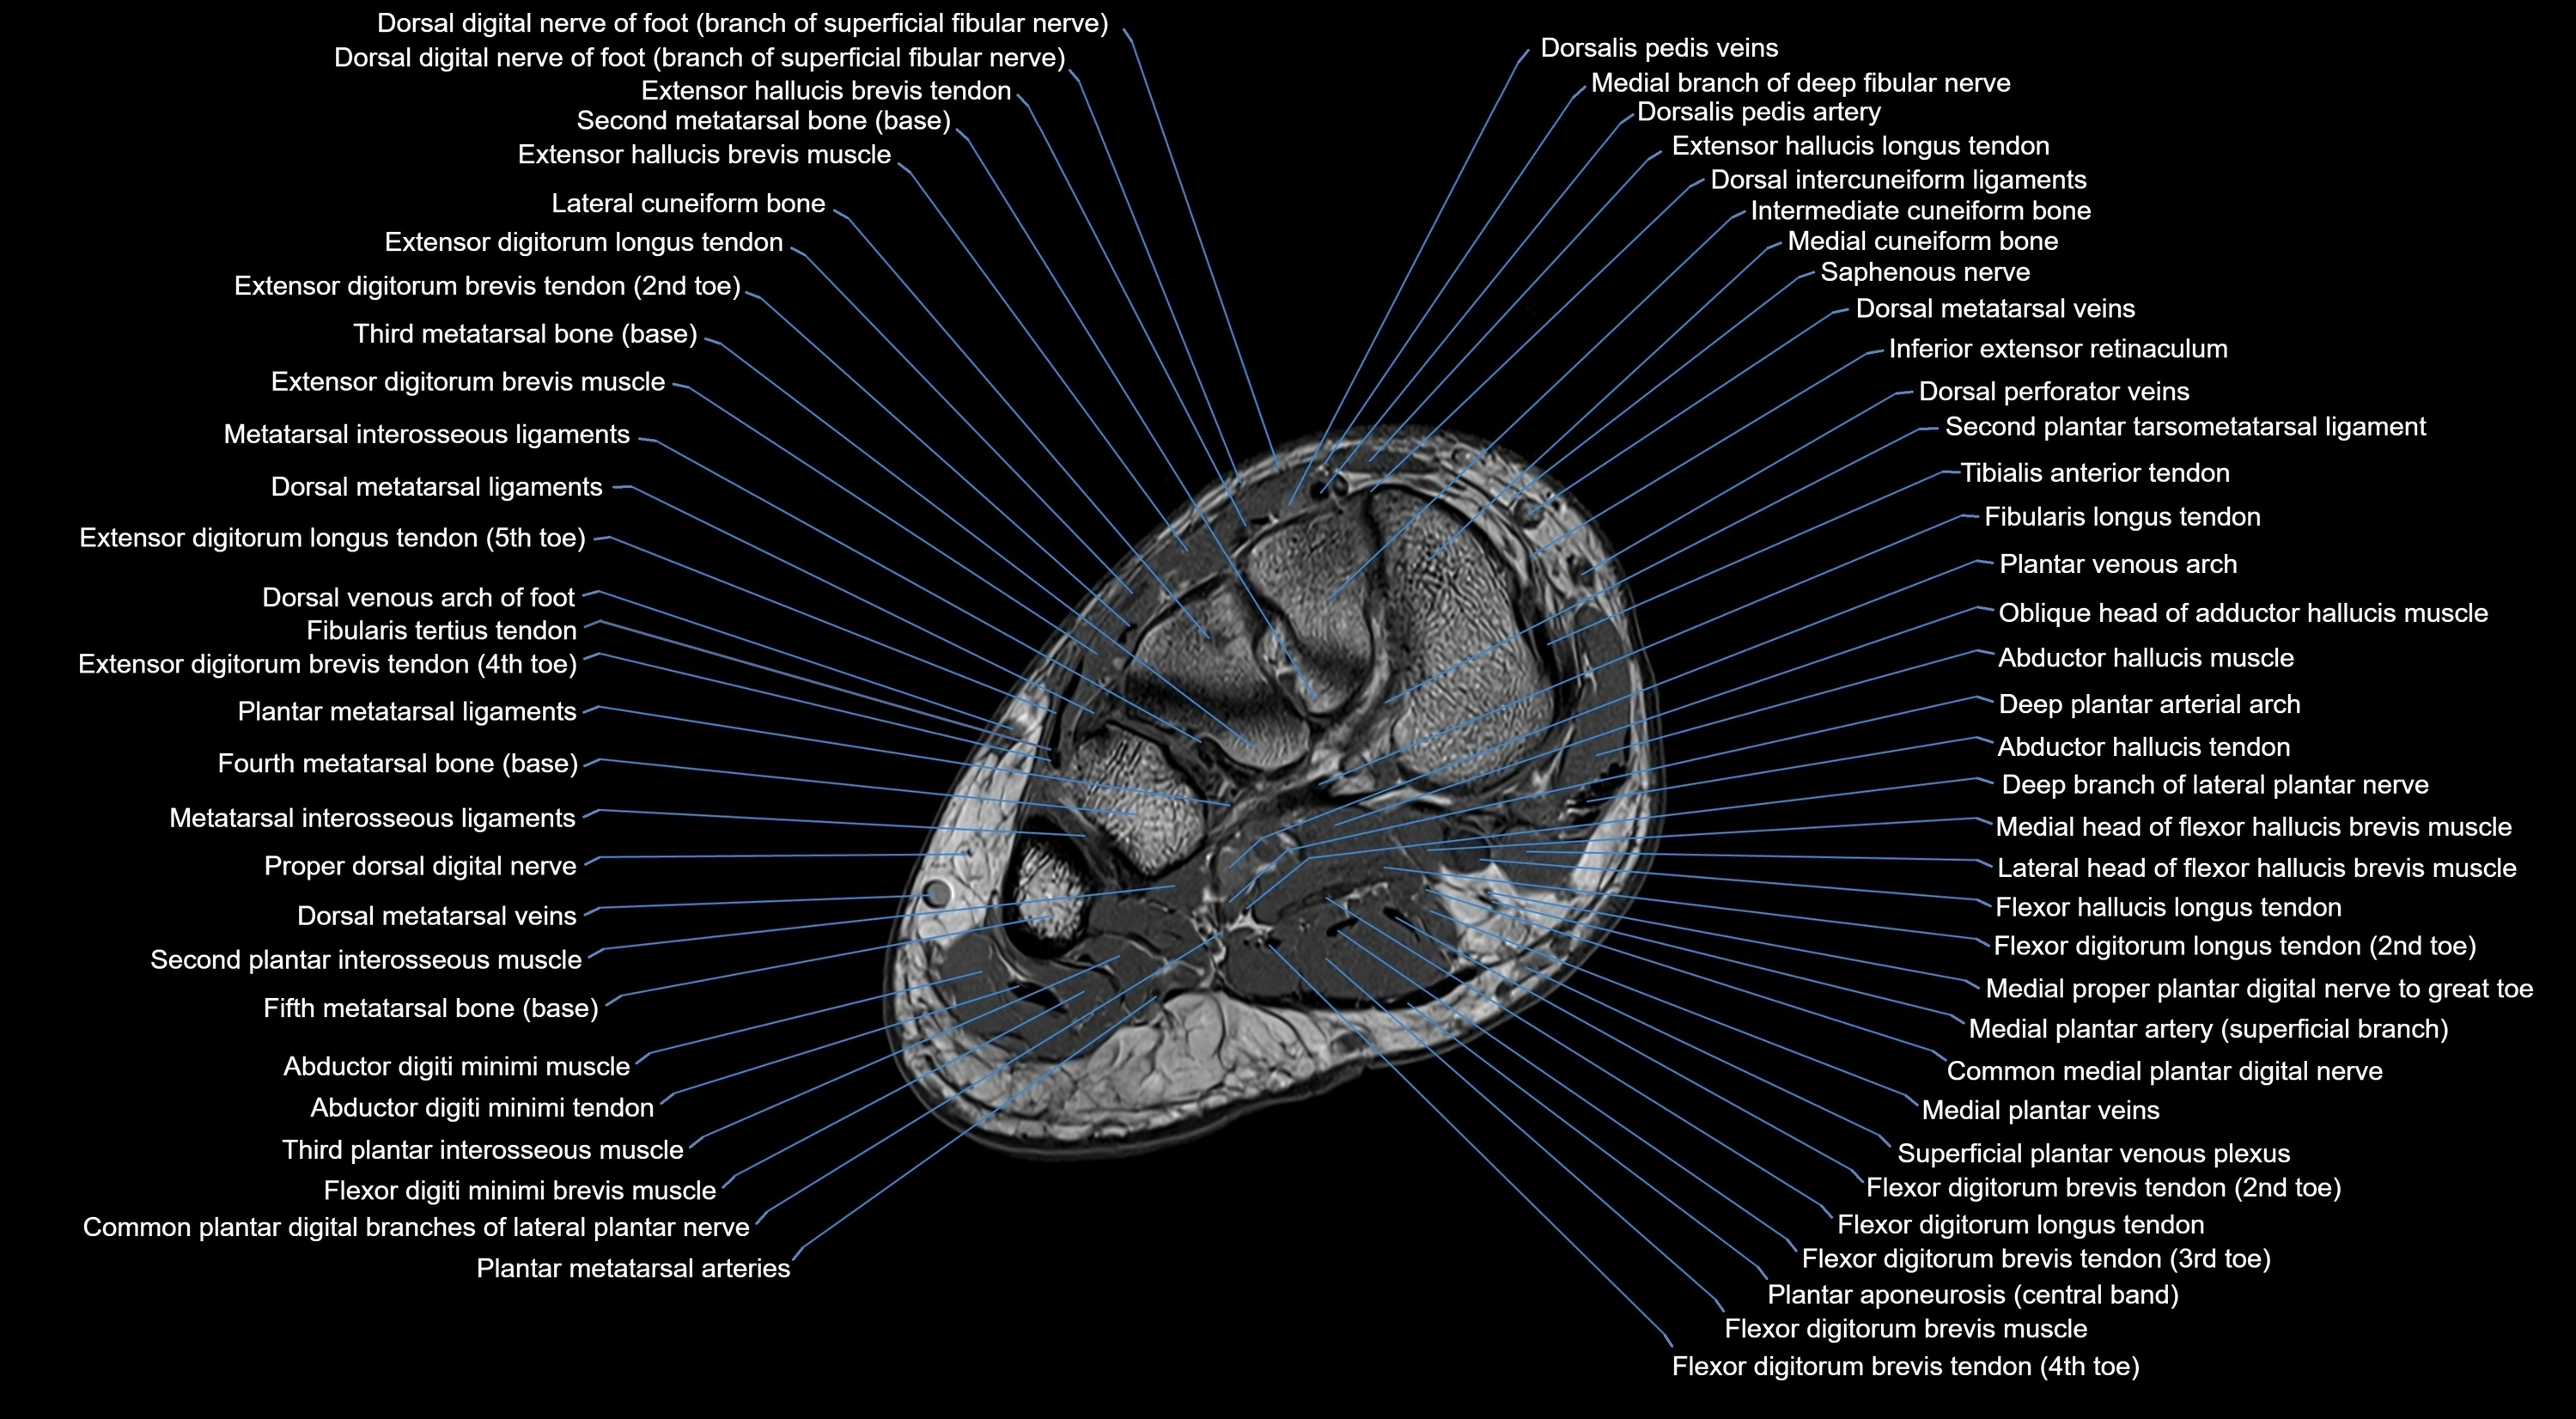

MRI image